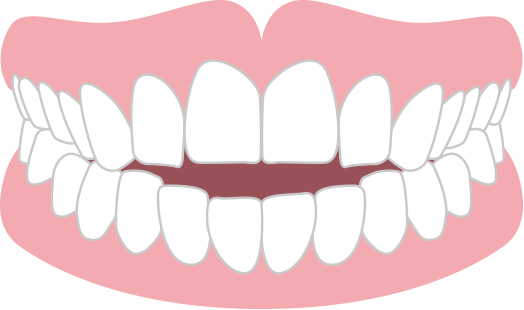

前歯が咬まない 開咬

奥歯で咬めてても前歯同士が当たっていない状態。 めん類や繊維質の食材が咬み切りにくく、また奥歯に負担が集中しやすいため、奥歯の寿命が短くなります。重度の開咬の方は矯正歯科治療が保険適用になります。